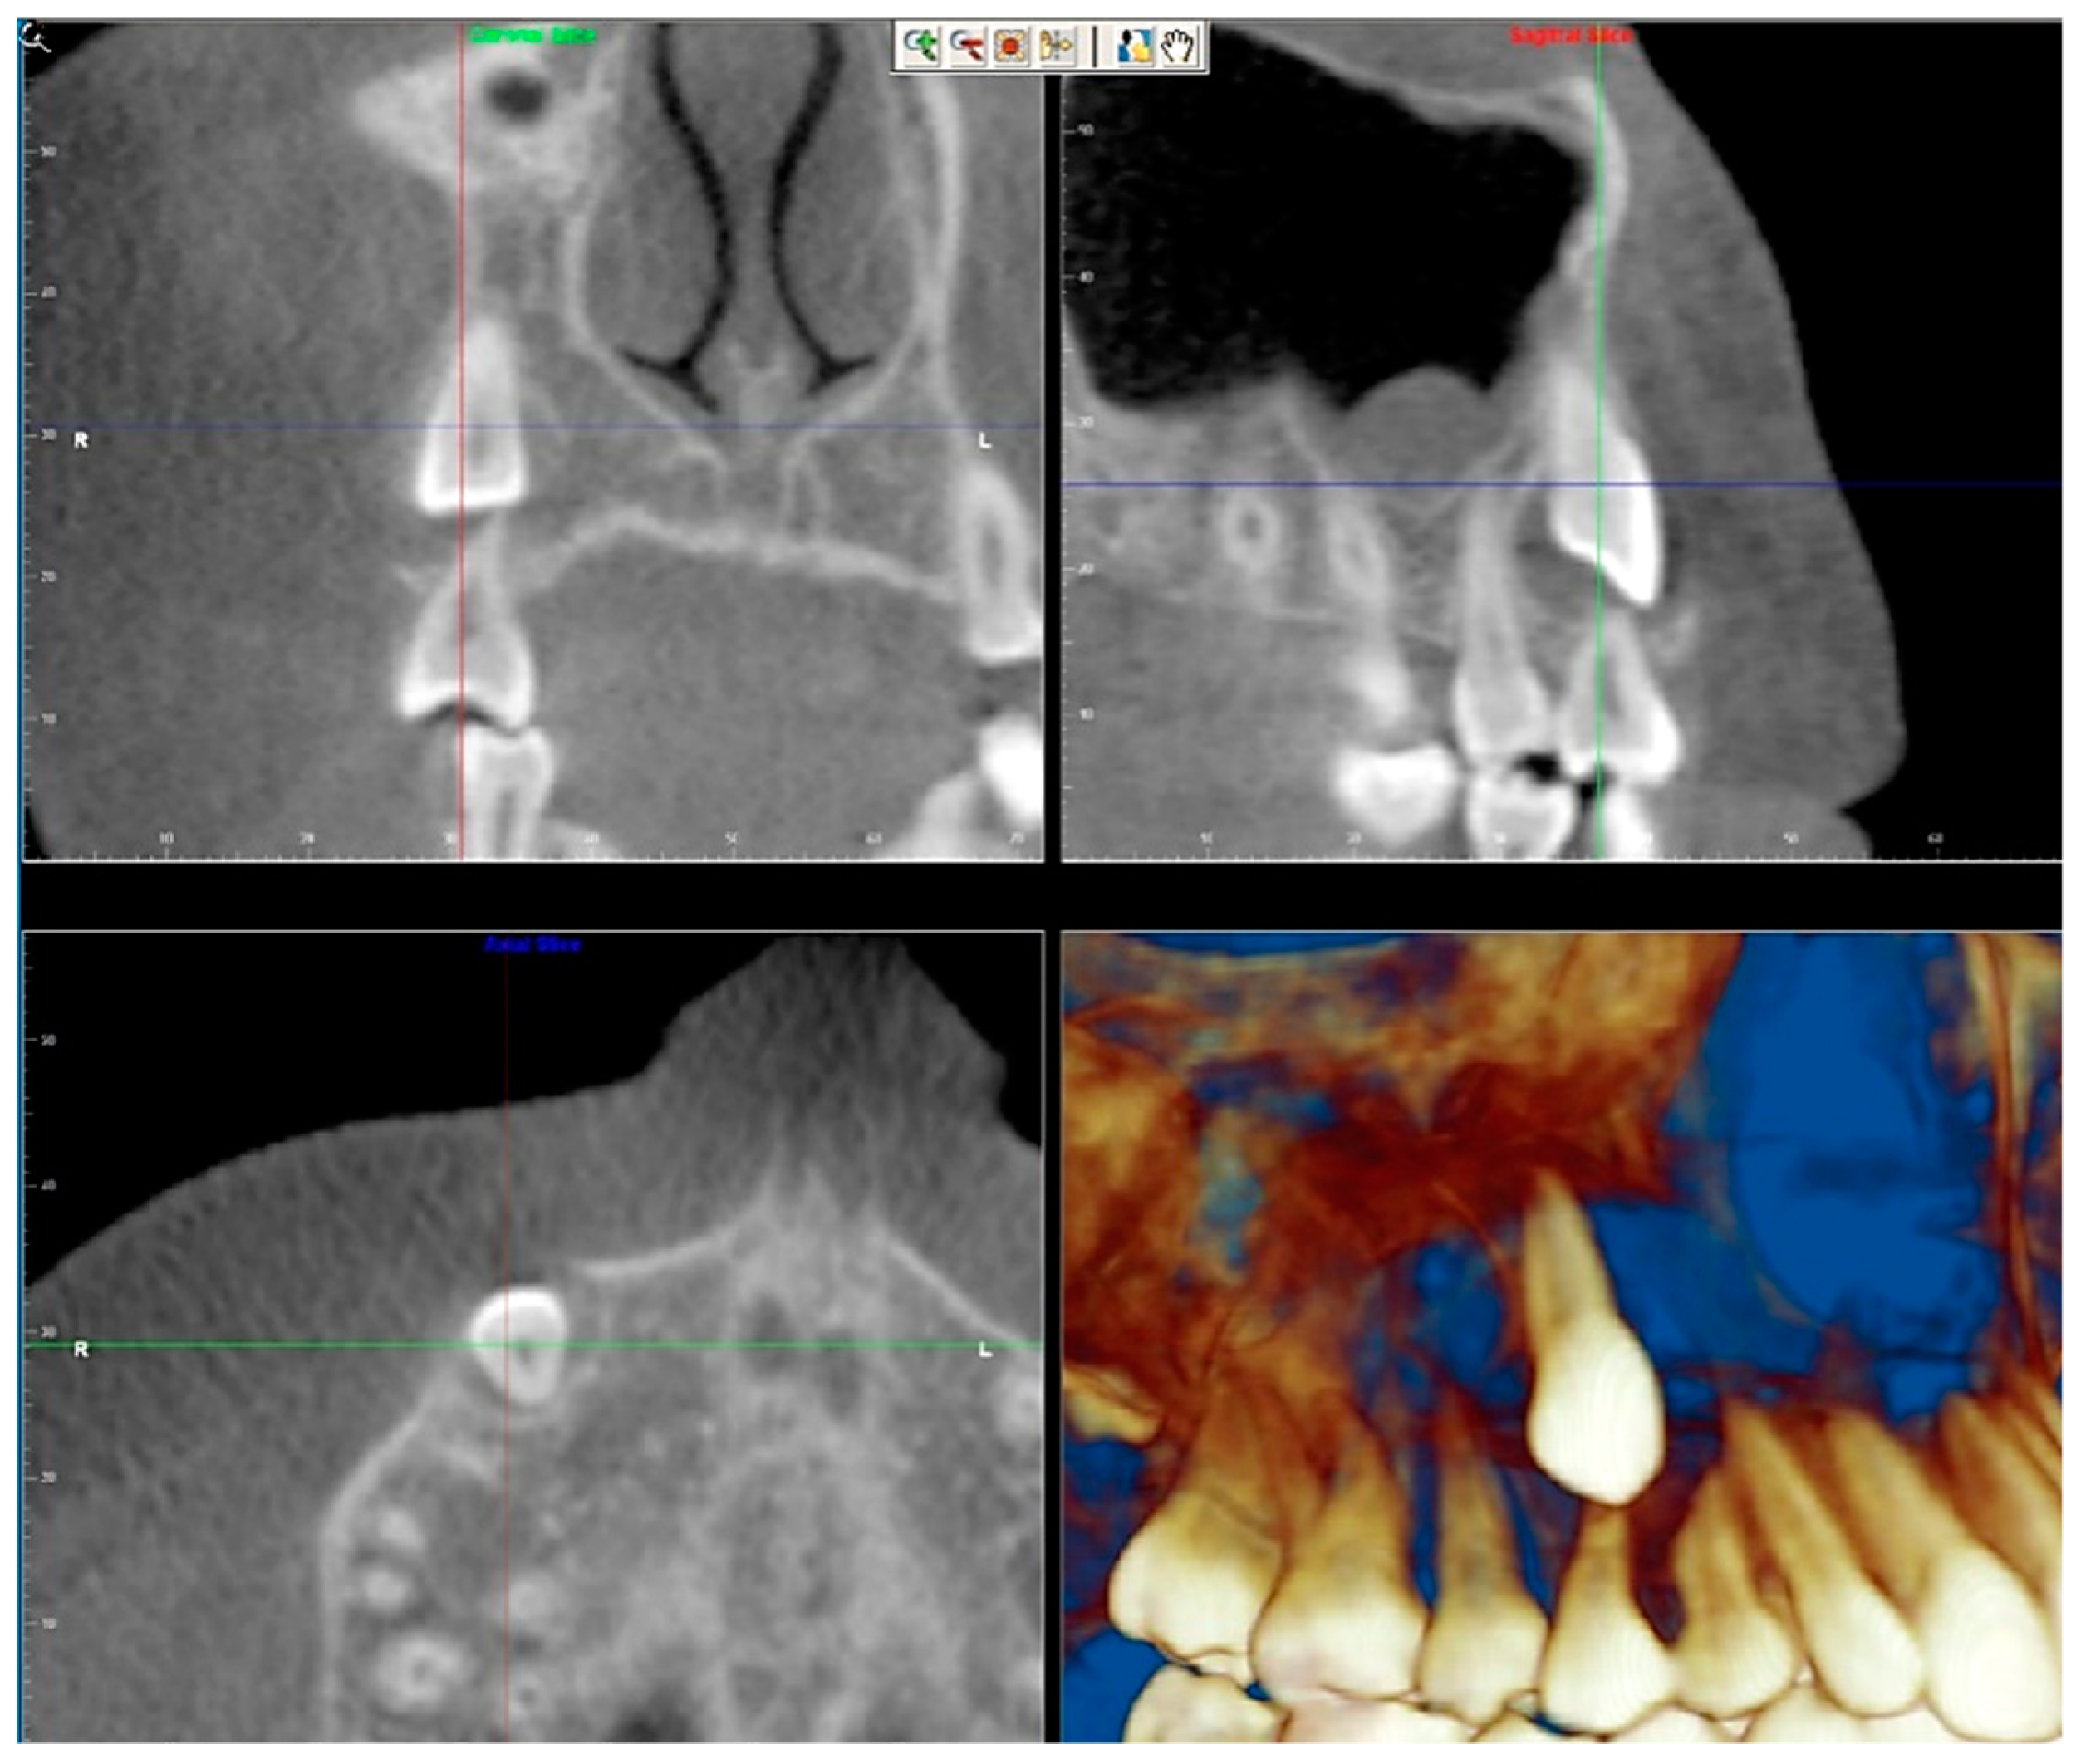

- Evaluation of impacted teeth, a common indication of CBCT in orthodontics. The advantages of CBCT include assessment of the tooth location and position, the stage of development, and status of adjacent teeth. CBCT is justified in these cases, because CBCT has the capability of evaluating the impacted teeth and adjacent structures more accurately than 2D conventional imaging. The benefit–risk ratio is favorable, especially if the CBCT volume is collimated to the impacted tooth. Figure 1, Figure 2, Figure 3 and Figure 4 show an example of impacted maxillary canines, and their proximity to the maxillary lateral incisors. Figure 1 shows an intraoral photograph. The benefit of CBCT acquisition in this case includes the ability to visualize the canines and the lateral incisors in three dimensions, which can be visualized in Figure 2 and Figure 3. In this case, the maxillary right lateral incisor exhibited external root resorption, a finding that would be difficult to see on a conventional 2D panoramic radiograph. Figure 4 shows a Maximum Intensity Projection of a panoramic view derived from the CBCT volume. This unique view is free of magnification, distortion, ghost images, and overlaps frequently seen in conventional 2D panoramic radiography.